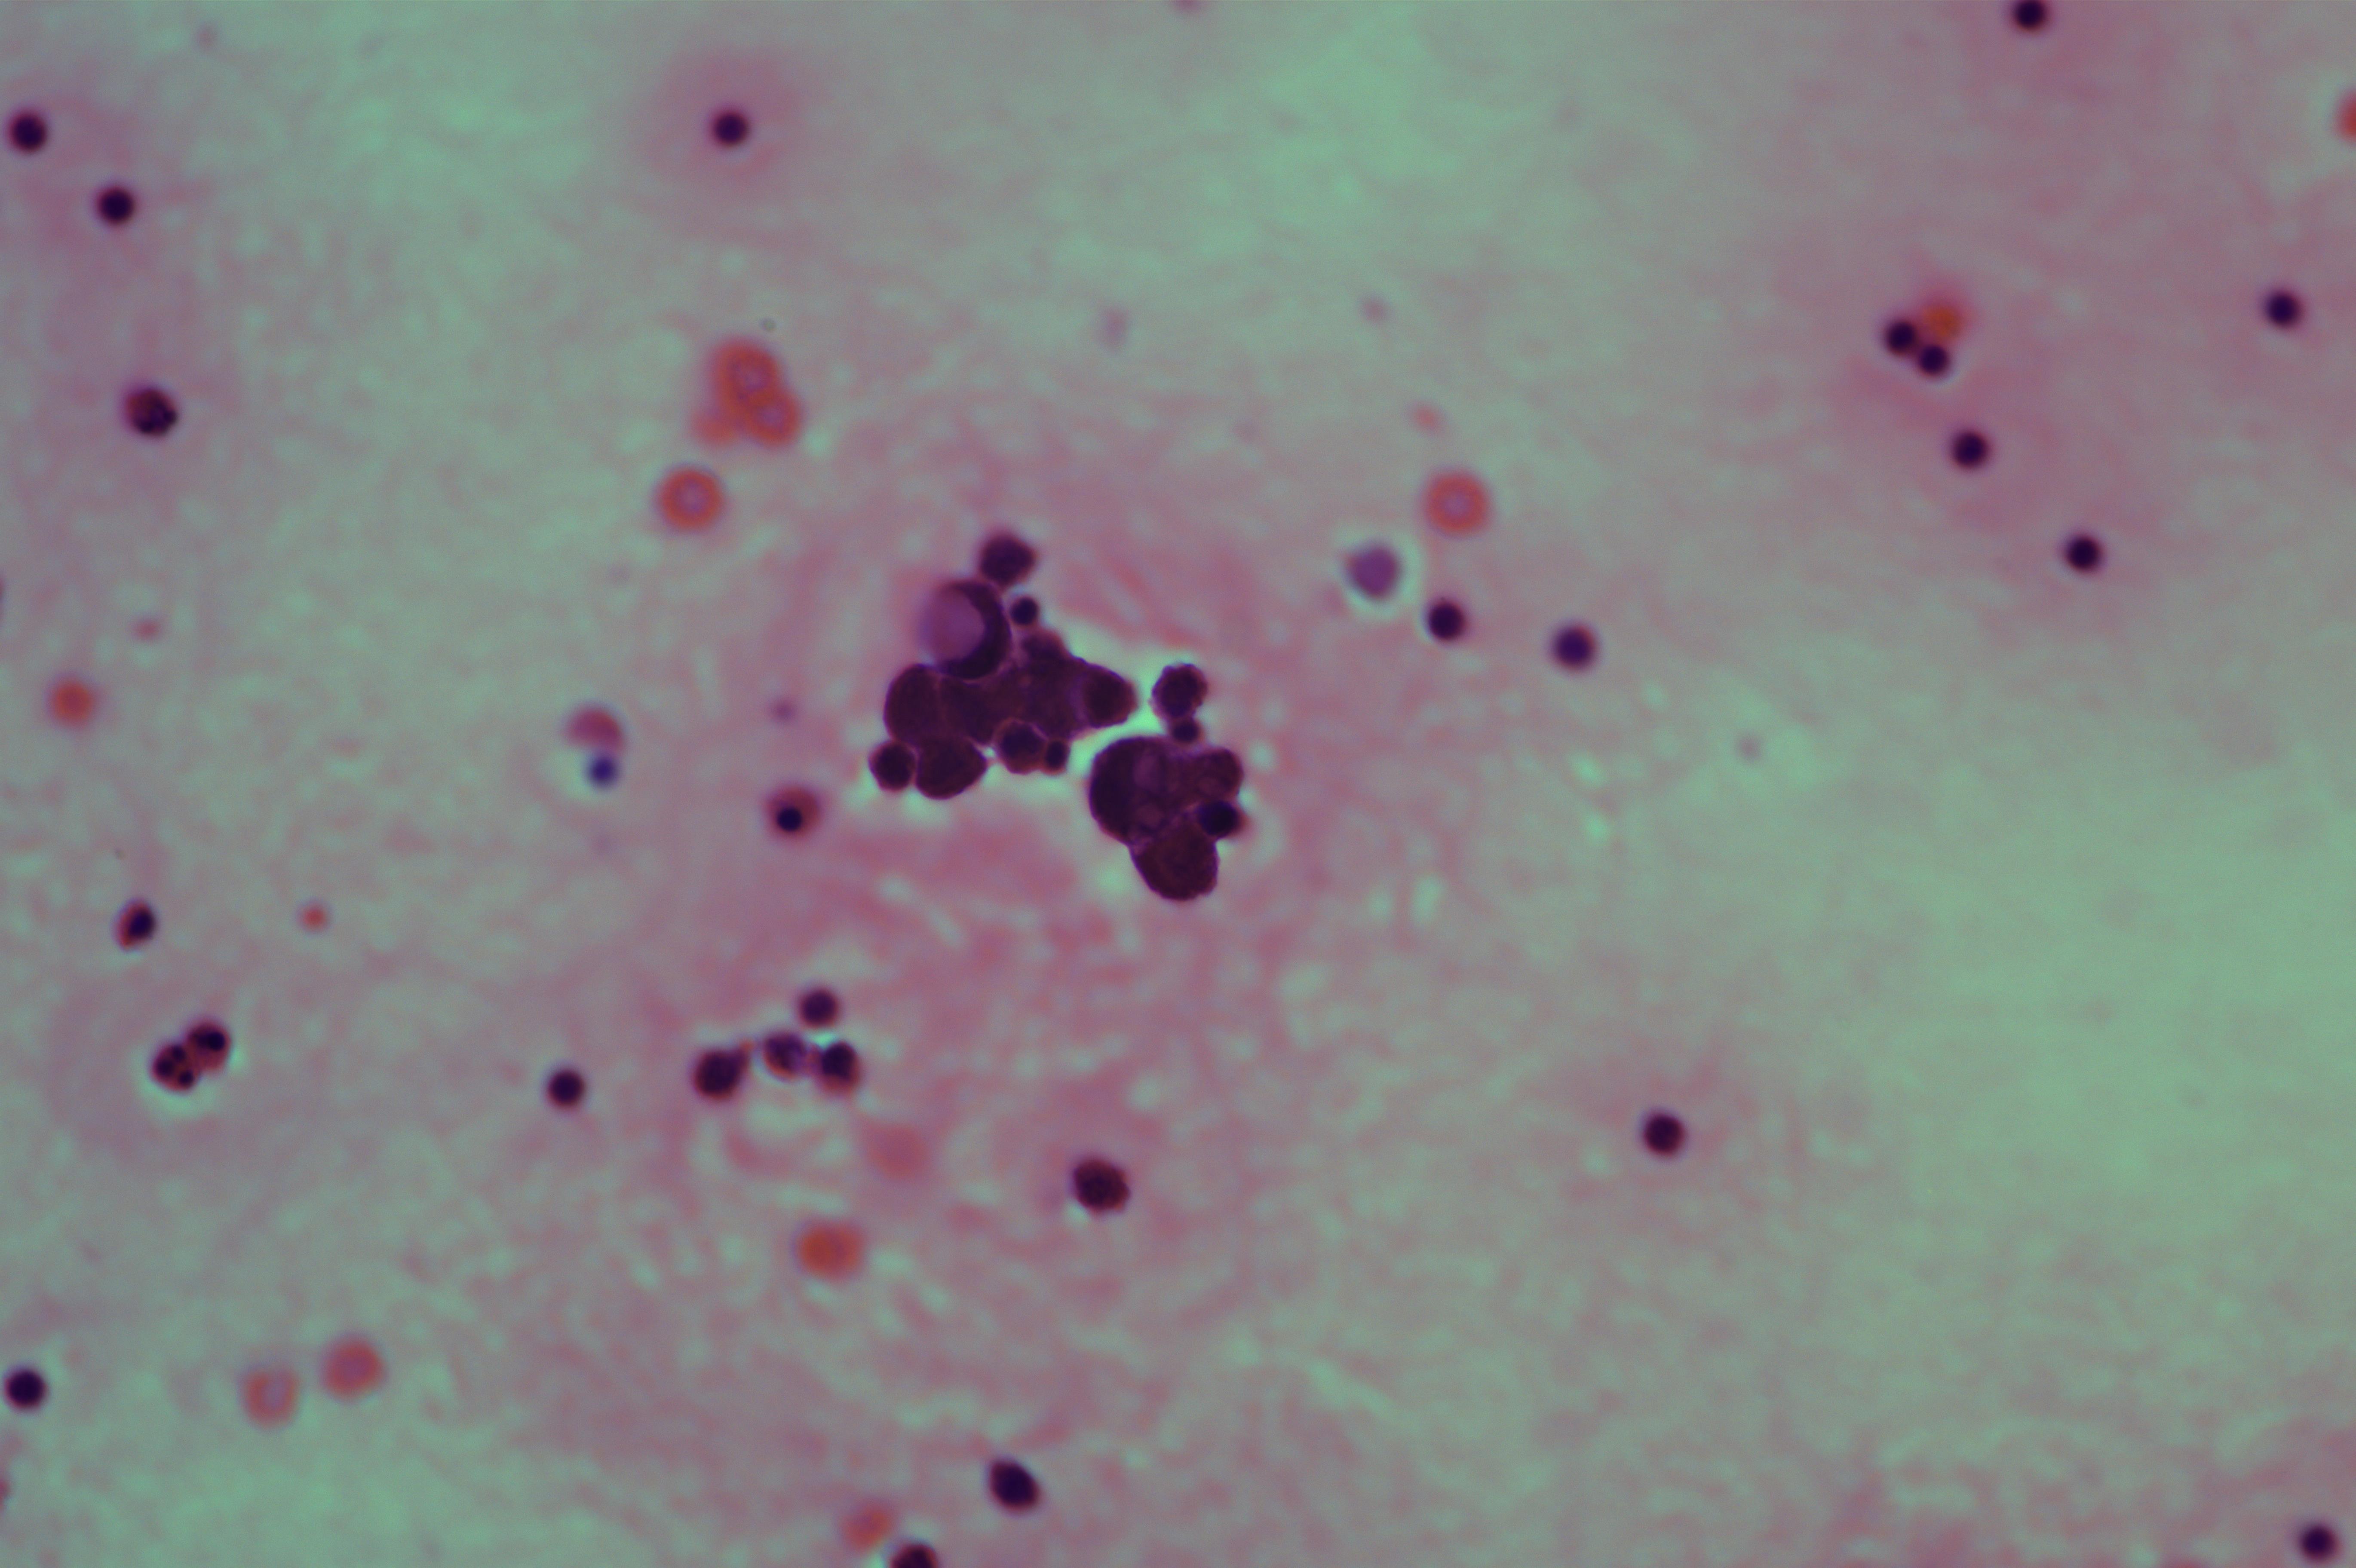

女,78岁,胸水腺癌

性别

女

年龄

78岁

一般病史

胃低分化腺癌术后一年

标本类型

胸水

制片方法

涂片

染色方法

HE

图1

考虑为腺癌

图3、图9是什么?